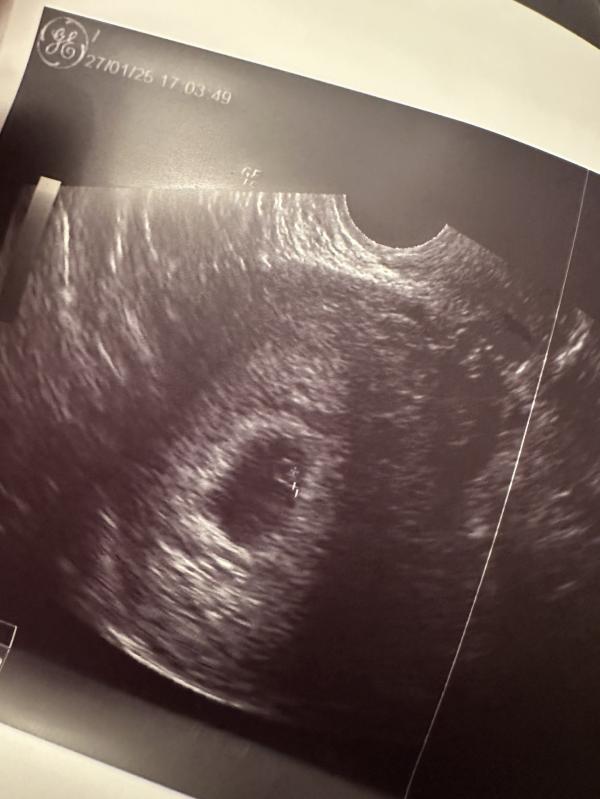

Первое фото малыша 🥹🤭❤️🥰

Спойлер: как видите по фото с узи все хорошо, про прием расскажу в следующем посте ❤️